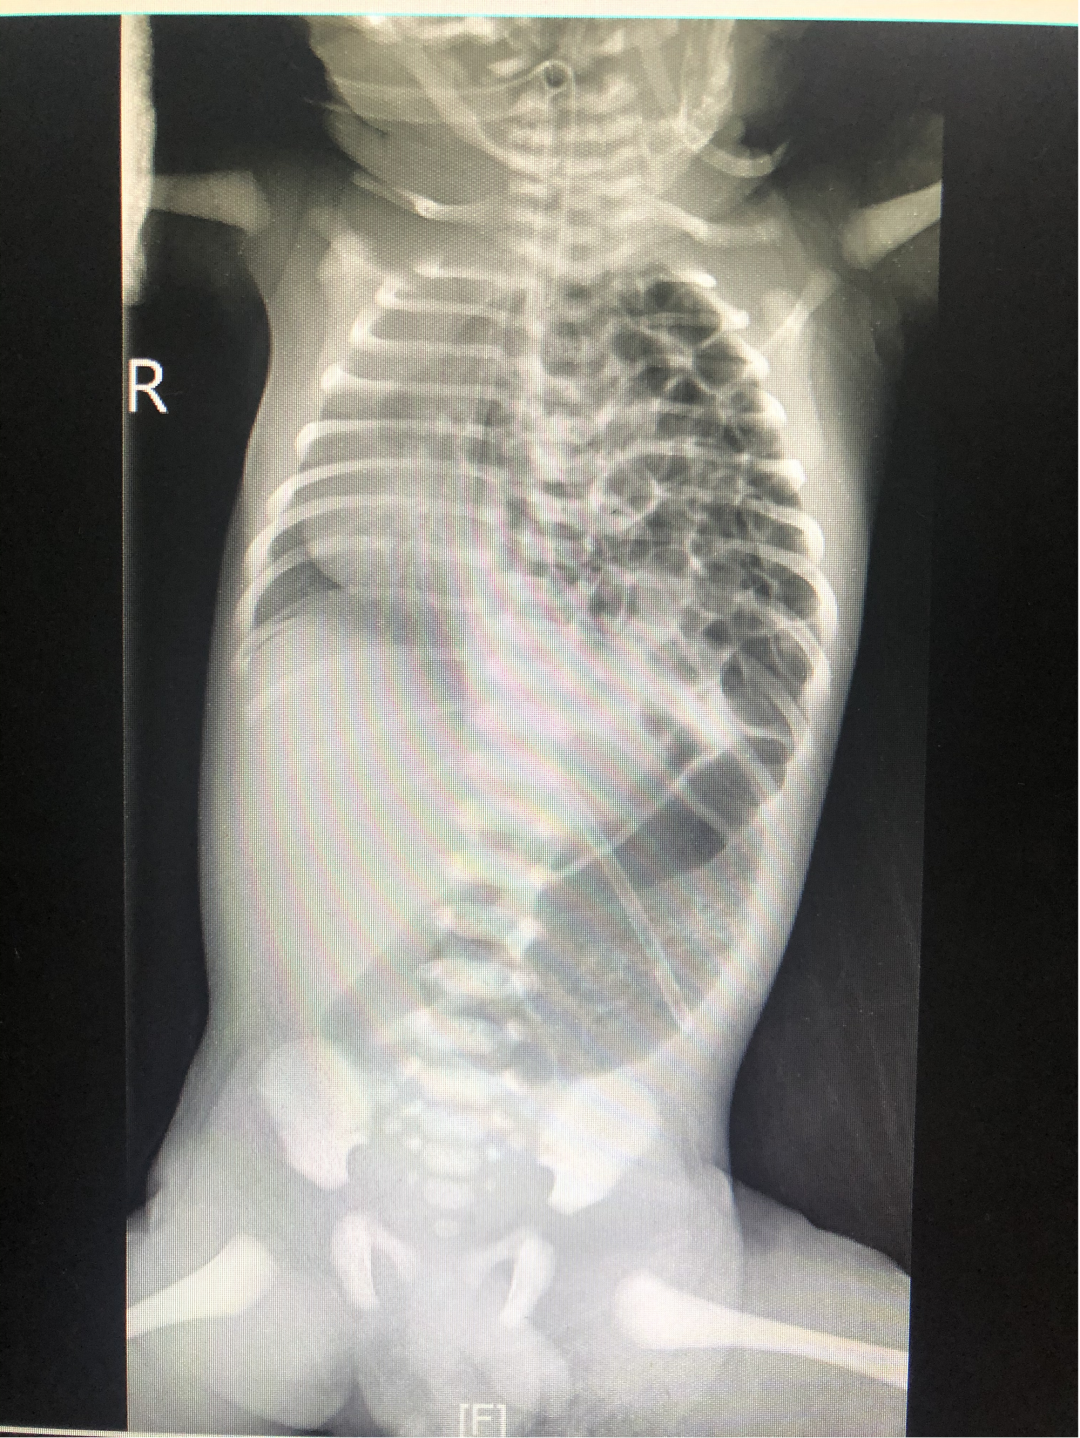

38+5W 2410g,外院剖宫产,Apgar评分10分,生后不久出现气促、紫绀,伴口吐白沫,于有创呼吸机辅助通气,胸片提示膈疝可能。经救护团队转至我院。完善术前准备,拟生后第二天行胸腔镜下膈疝修补术。

现代的产前检查非常仔细,CDH一般都能在产前通过超声或MR检查诊断出来。任何出生后不久即出现呼吸衰竭征象的新生儿,应该考虑其是否患有CDH的可能。左侧膈疝的患儿查体往往可以看到舟状腹和桶状胸,而且左侧呼吸音降低或缺如。胸片显示扩张的肠管位于左侧胸腔,纵隔右移。